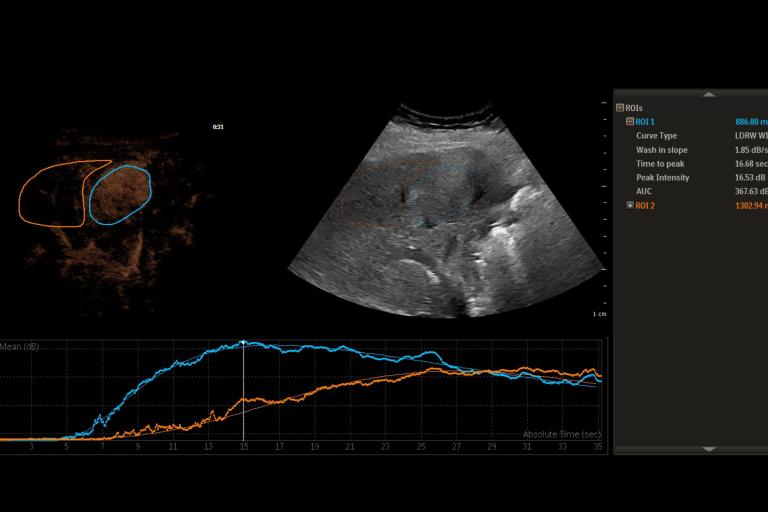

- Quantitative contrast-enhanced ultrasound for organ and tumor perfusion analysis

- Contrast-enhanced ultrasound motion correction and frame filtering